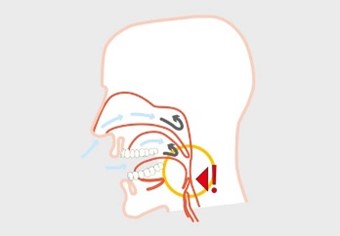

Silensor se sastoji od jedne zubne udlage za gornju čeljust i jedne zubne udlage za donju čeljust. Donja čeljust se zadržava u prednjem položaju (protruzija) s dvije spojnice koje su fiksirane bočno na udlagama. Na taj način silensor sprječava približavanje stijenki mekih tkiva. Sa silensor udlagom pokreti donje čeljusti su mogući lijevo-desno i naprijed bez povlačenja unatrag.

Zbog ove funkcije silensor je istodobno učinkovit i udoban. Klinički testovi su pokazali da potiskivanje donje čeljusti prema naprijed značajno smanjuje hrkanje za kod više od 90% pacijenata i može smanjiti indeks apneje za 50%